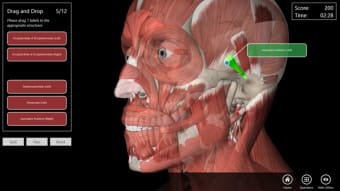

Essential Anatomy 3 bukanlah revolusi dalam rangkaian aplikasi Essential Anatomy tetapi menambahkan lebih banyak detail dan kemudahan penggunaan ke aplikasi. Hal yang paling mengesankan tentang Essential Anatomy 3 adalah tingkat detail dan model 3D yang dapat Anda manipulasi dan jelajahi. Essential Anatomy 3 tidak meninggalkan organ atau tendon terbuka - tingkat detailnya sama bagusnya dengan apa pun yang Anda temukan di Ensiklopedia medis.

Untuk mahasiswa kedokteran khususnya, Essential Anatomy adalah alat referensi yang luar biasa. Model 3D memungkinkan Anda untuk melihat dan memeriksa bagian tubuh manusia dari sudut mana pun memberikan detail luar biasa yang biasanya hanya dapat Anda alami melalui pembedahan.

Jika Anda perlu menemukan tulang, organ tertentu atau otot, Anda cukup menelusuri berdasarkan bagian tubuh dan Essential Anatomy akan menyorot dengan tepat di mana mereka berada dengan deskripsi bermanfaat dari setiap bagian. Satu-satunya hal yang kurang adalah animasi organ dan otot yang sedang beraksi.

Essential Anatomy sangat mudah digunakan. Fungsi pencarian adalah yang paling Anda butuhkan jika Anda sedang belajar meskipun Anda dapat bersenang-senang hanya dengan menjelajahi dan memutar tubuh. Anda dapat melepaskan lapisan otot dan jaringan untuk mengungkapkan apa yang ada di bawahnya, yang memberi Anda gambaran yang lebih baik tentang cara kerja tubuh daripada hanya membacanya di buku.

Selain itu, ada Alat penanda jika Anda hanya ingin menyimpan bagian tertentu yang ingin Anda kembalikan nanti dan Anda dapat mengisolasi tampilan tubuh berdasarkan jenis bagian (misalnya otot, arteri, vena, dll.).